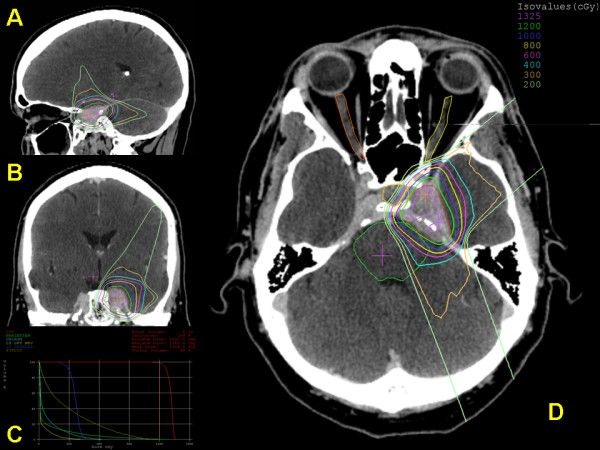

额骨骨瘤内镜切除技术---我的手术技术学习笔记系列